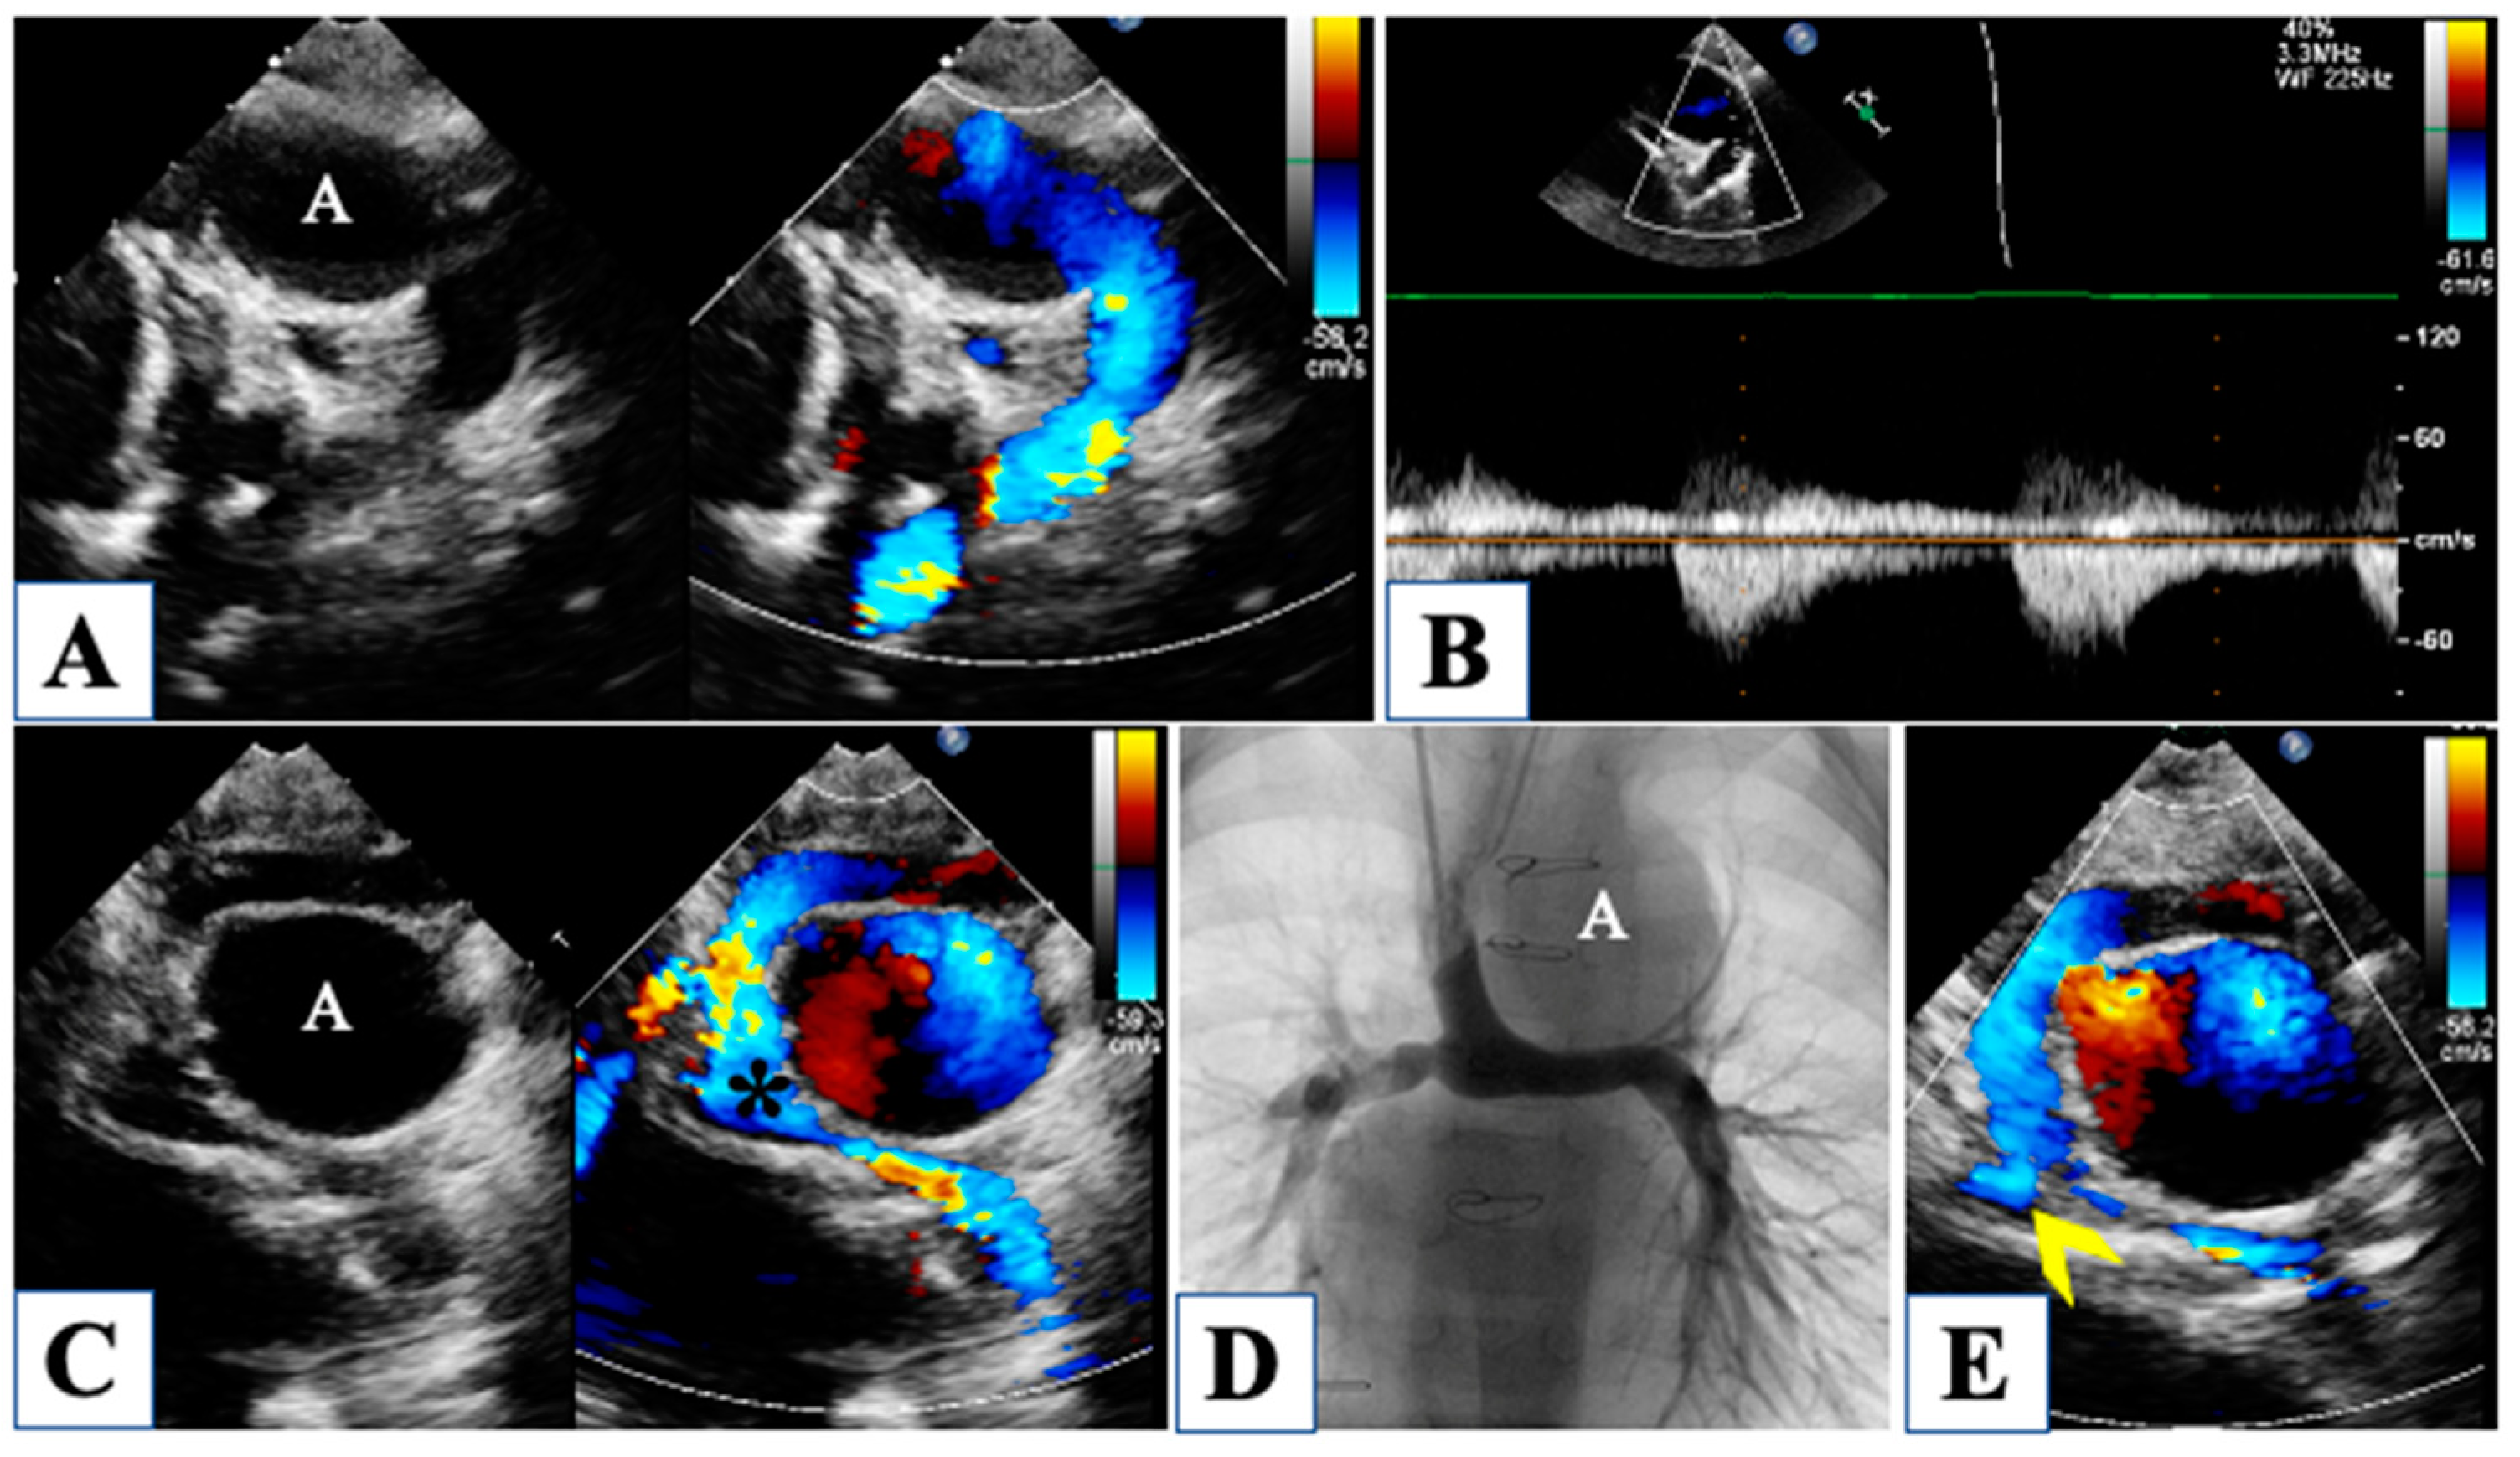

| Oreto et al., 2023 | [16] | Pre-stage I | Left ventricle, aortic and mitral valves, long axis ratio | Aortic annulus, mitral annulus, aortic root, left ventricular/heart long axis, left ventricular volumes, and mass | Evaluation of the borderline left ventricle |